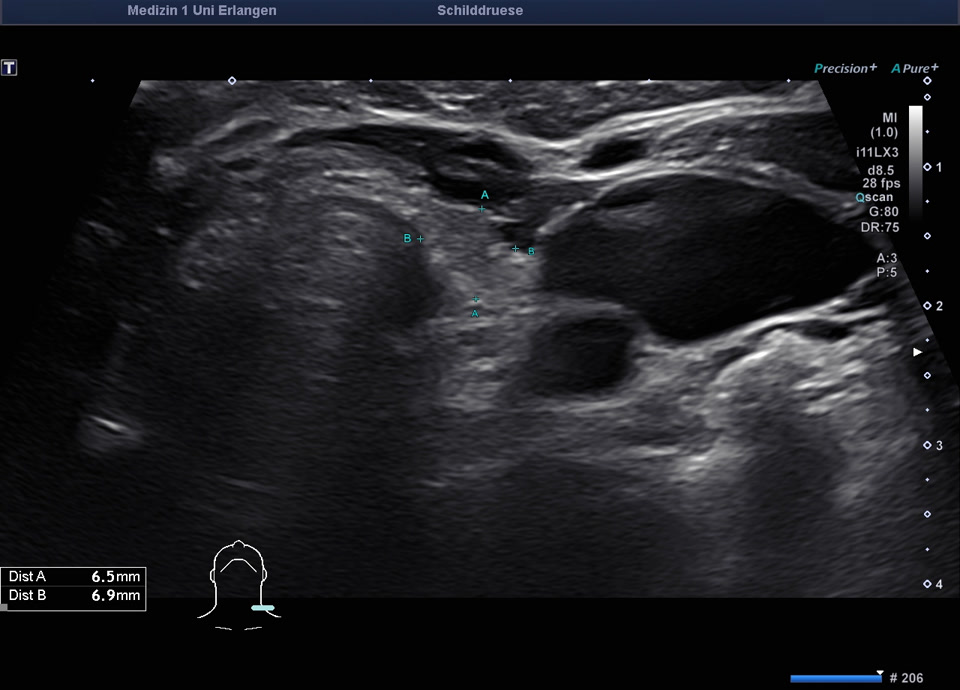

36-jähriger Patient mit Tremor, Tachykardie, Exophthalmus und Gewichtsverlust. Sonographisch stellt sich die Schilddrüse beidseits mit echoarmer inhomogener Parenchymstruktur dar. Gesamtvolumen 20,5 ml. Farbdopplersonographisch hypervaskularisiert. Laborbefunde: basales TSH erniedrigt, T3/fT4 erhöht, TRAK positiv. Befundkonstellation vereinbar mit M. Basedow. Unter Therapie mit Thiamazol und Propranolol beschwerdefrei. Bei Verlaufskontrolle zwei Jahre später sonographisch echoreiches minimal inhomogenes Parenchym bei normalem Volumen (15 ml).